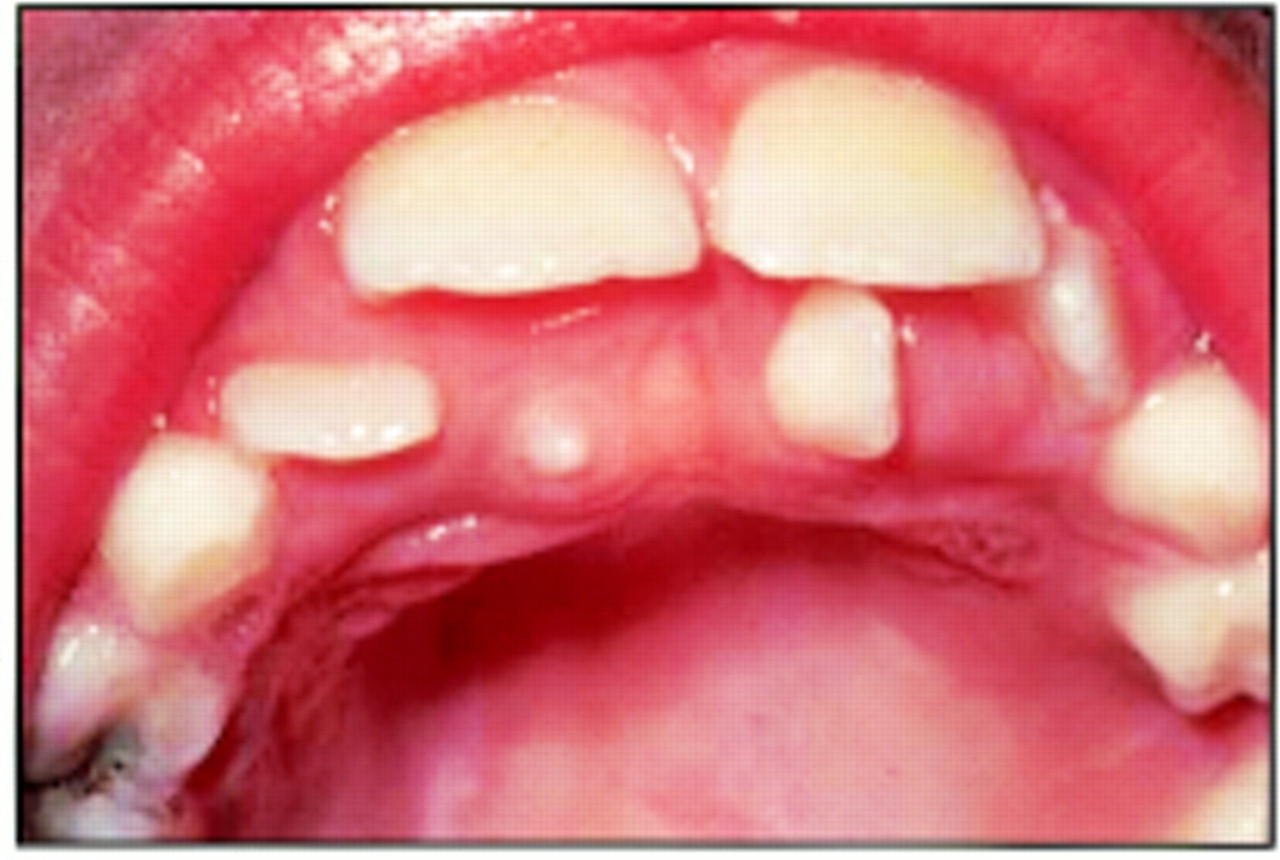

Pseudoanodontia is a descriptive term that indicates clinical but not radiographic absence of teeth that should normally be present in the oral cavity for the patient’s dental and chronologic age. In these cases, radiographic examination discloses the teeth in the jaws. These persons might have retained their deciduous teeth; more commonly, the deciduous teeth have been shed, but the permanent ones failed to erupt.